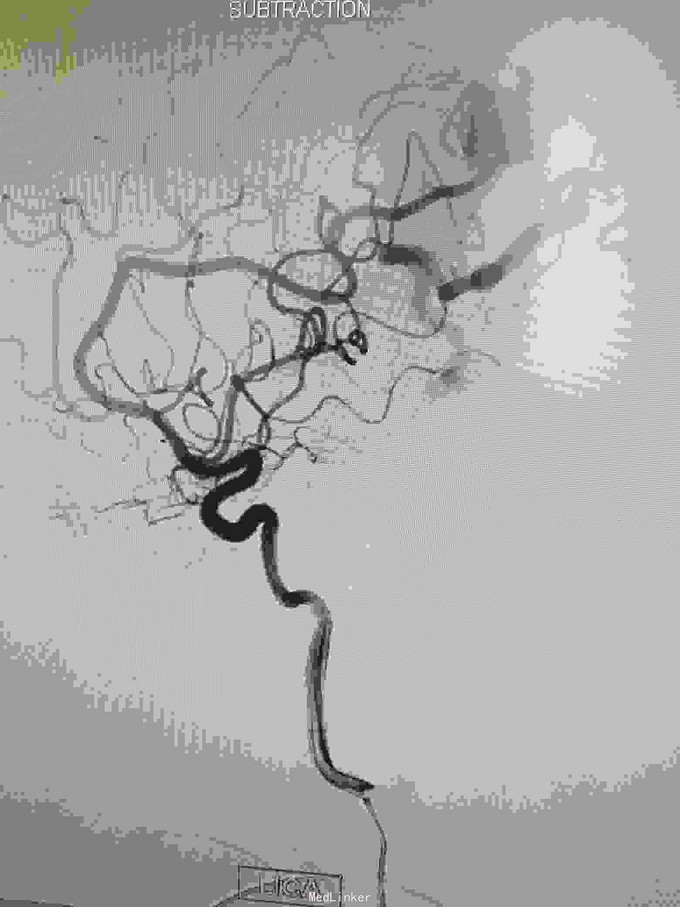

左枕顶区AVM。 左大脑后及左大脑前供血,深部静脉回流。

AVM治疗如能栓塞治疗创伤较小,手术切除虽较完全,但损伤是不可突视的问题。